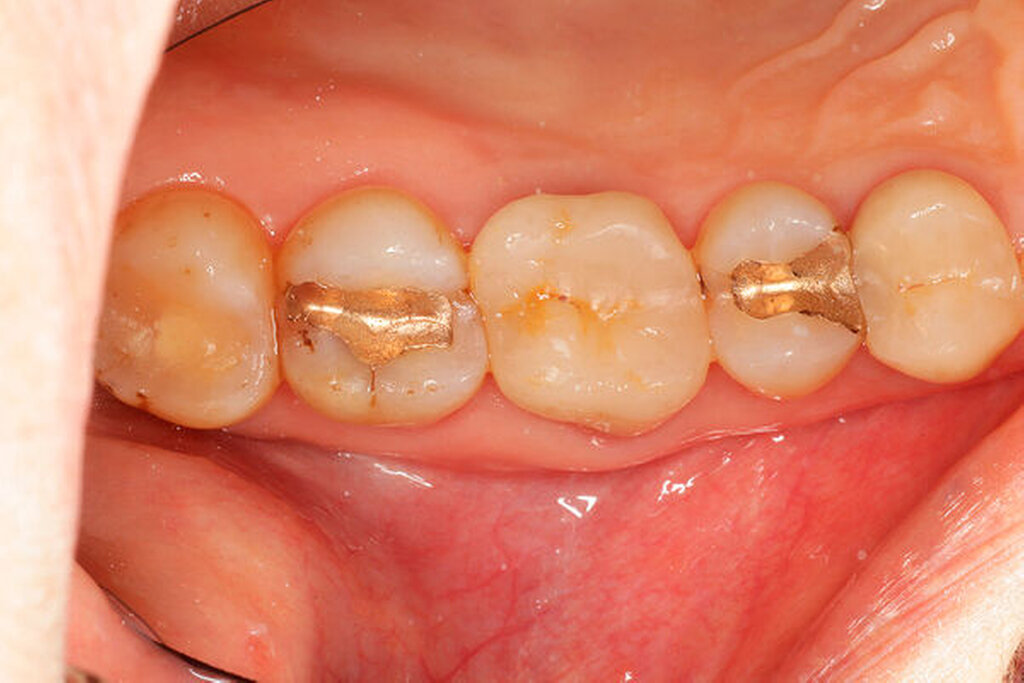

Ein 59-jähriger Patient stellte sich erstmals 2015 mit rezidivierenden pochenden Beschwerden und zeitweise zusätzlich auftretendem Pusaustritt an Zahn 16 vor. Klinisch zeigte sich ein ausgeprägter Attachmentverlust distal mit bis apikal sondierbarer distobukkaler Wurzel, Furkationsbeteiligung und Pusaustritt sowohl über den Parodontalspalt als auch durch einen distobukkal gelegenen Fistelausgang. Zunächst erfolgte die endodontische Behandlung des Zahnes 16 mit anschließender systematischer PA-Therapie. Bei persistierender parodontaler Problematik an 16 wurde die Möglichkeit der Teilamputation der distobukkalen Wurzel mit dem Patienten diskutiert, um die Hygienefähigkeit und damit die Prognose des Zahnes zu verbessern. Auch über die Extraktion als Alternative wurde der Patient aufgeklärt. Er war allerdings motiviert, seinen Zahn so lange wie möglich zu erhalten.

So erfolgte die Amputation der distobukkalen Wurzel mit anschließender Versorgung des Zahnes mittels Vollkrone. Die Situation an 16 ist seitdem für den Patienten subjektiv stabil, die aktuelle Röntgenkontrolle zeigt jedoch eine Progredienz der parodontalen Defekte trotz regelmäßiger UPT und subjektiv guter Mitarbeit des Patienten, was die Prognose des Zahnes negativ beeinflusst. Ursächlich hierfür kann eine persistierende parodontale Infektion durch den trotz Wurzelamputation immer noch schwer für die häusliche Mundhygiene zugänglichen Furkationsbereich mit enger Lagebeziehung der mesiobukkalen und der palatinalen Wurzel sein. Der Patient ist allerdings aktuell mit der Situation zufrieden und beschwerdefrei und wünscht daher noch keine Extraktion des Zahnes, auch wenn diese sich nun fünf Jahre nach dem initialen Befund nicht mehr sehr lange vermeiden lassen wird.